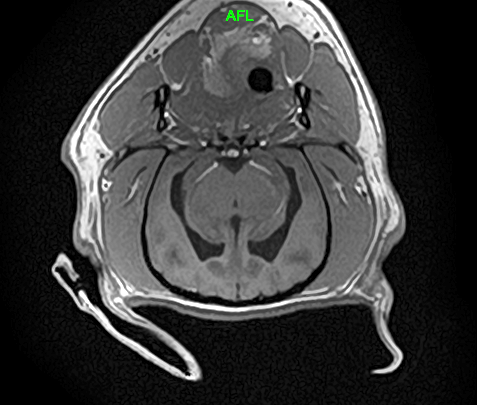

L’IRM (Imagerie par Résonance Magnétique) est un examen d’imagerie médicale très performant qui permet d’obtenir des images détaillées de l’intérieur du corps de votre animal, sans utiliser de rayons X. Elle est donc totalement indolore et non invasive.

L’appareil fonctionne grâce à un champ magnétique et à des ondes radio, un peu comme un grand appareil photo très précis, capable de « voir » les organes, le cerveau, la moelle épinière, les articulations et les tissus mous avec beaucoup de finesse. Les images obtenues permettent au vétérinaire de mieux comprendre l’origine des symptômes de votre animal.

L’IRM est un examen de référence pour explorer de nombreuses maladies, notamment neurologiques, articulaires ou musculaires, et constitue une aide précieuse pour proposer le traitement le plus adapté à votre animal.